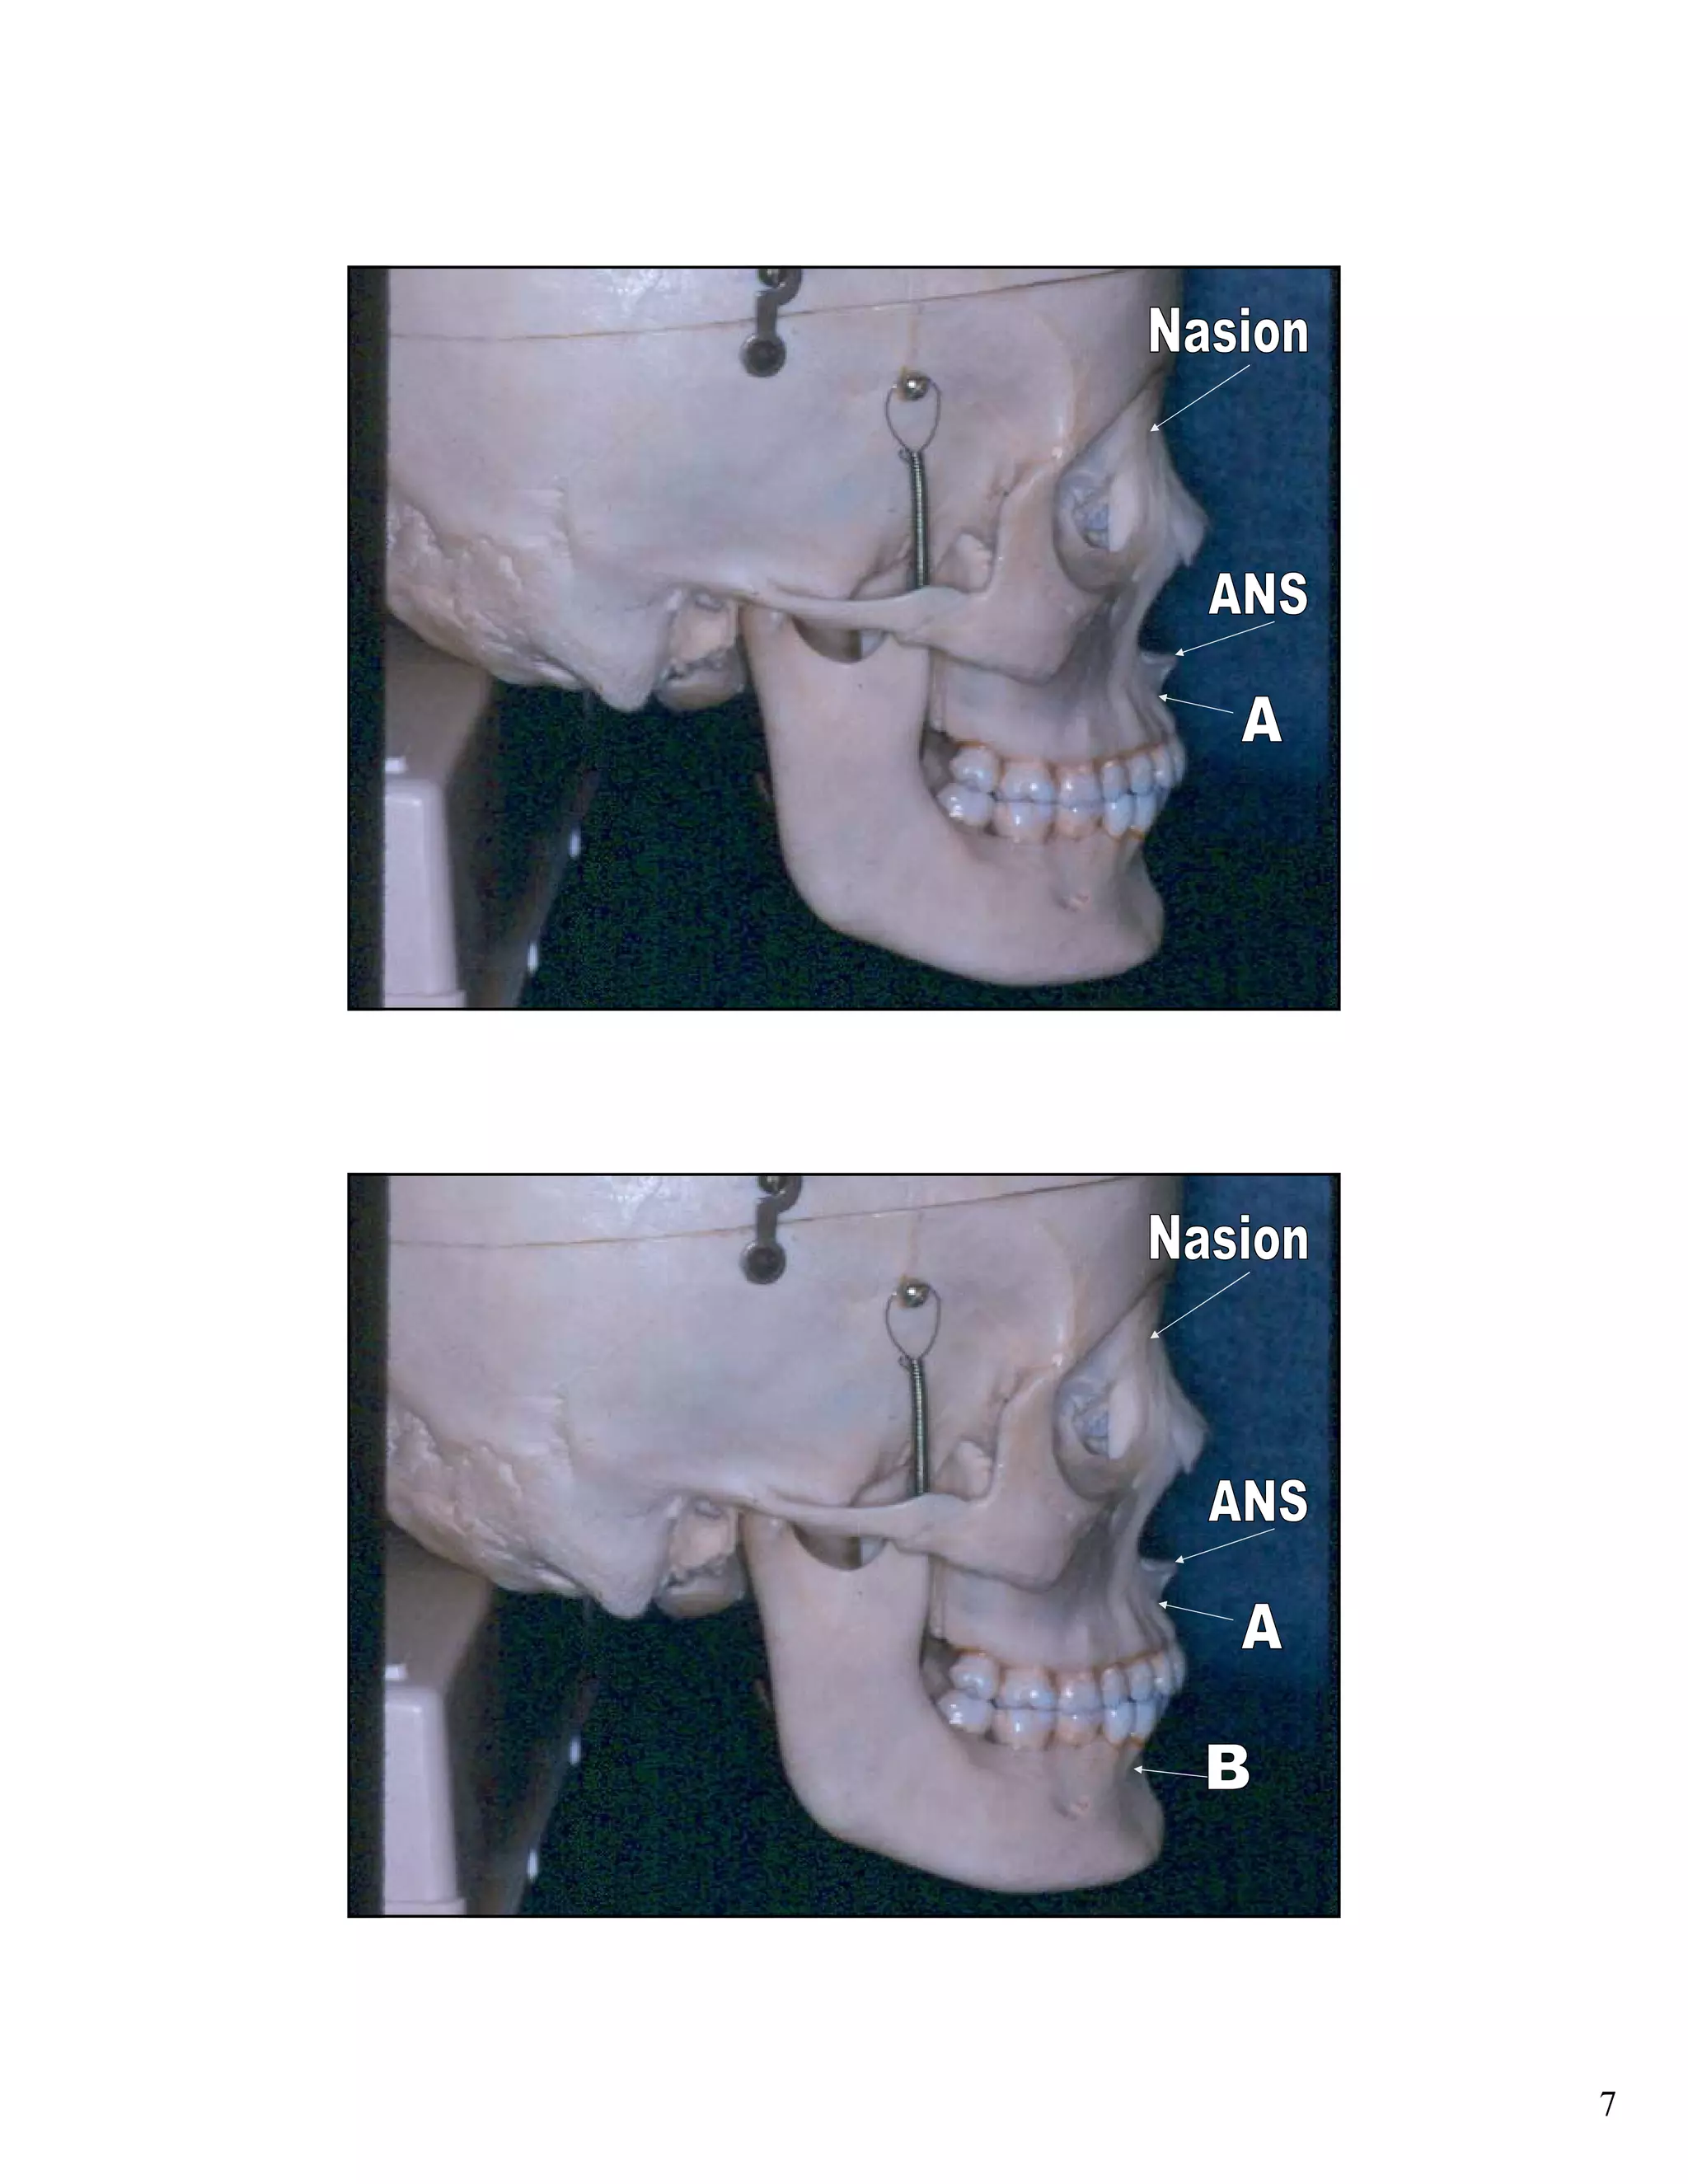

Cephalometric analysis uses x-rays of the skull to measure the growth and development of facial structures. Key indicators include the SN:GoGn angle measuring lower facial growth direction, the S-Go/N-Me ratio comparing posterior and anterior facial heights, and extension of the GoGn line to the occiput. These measurements help assess growth trends and plan orthodontic treatments.